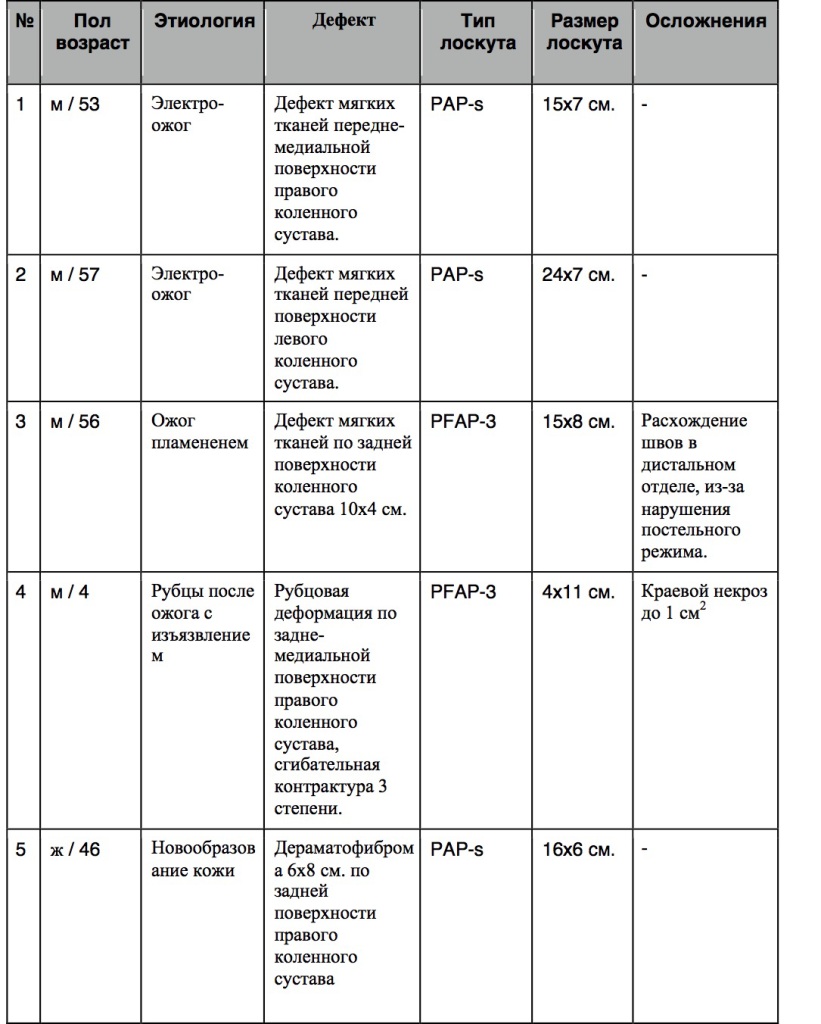

МАТЕРИАЛЫ И МЕТОДЫ: За период с 2011 по 2013 в клинике с целью закрытия обширных дефектов кожи и мягких тканей в области коленного сустава прооперированы 7 пациентов, у которых выполнена пластика с применением заднего перфорантного лоскута бедра: на третьем перфоранте глубокой артерии бедра и на перфоранте подколенной артерии. Характеристика лоскутов представлена в таблице 1.

Таблица 1.

Характеристика примененных задних перфорантных лоскотов бедра